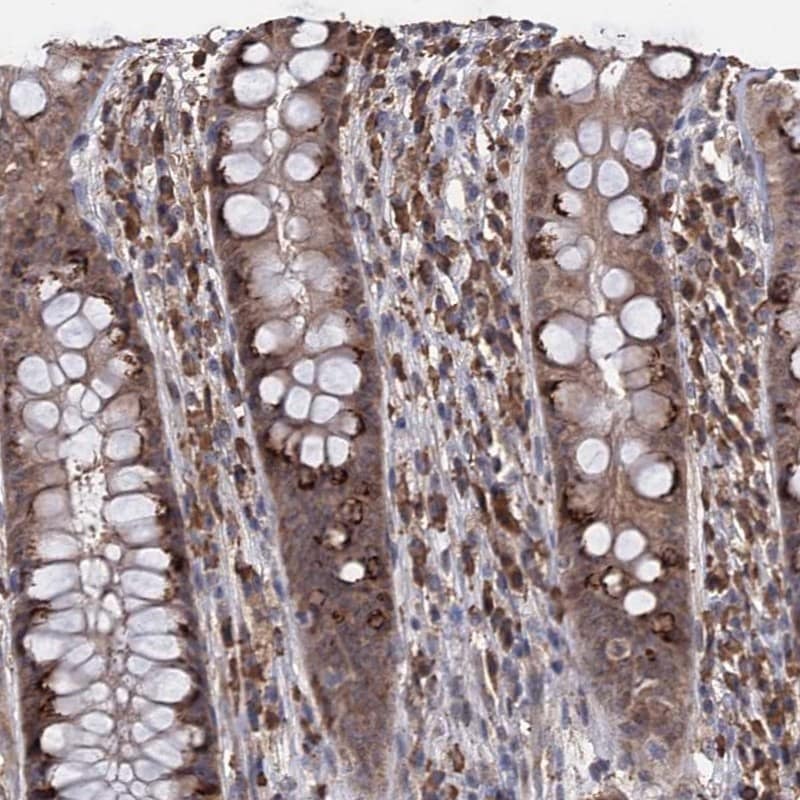

- Immunohistochemical staining of TBC1D12 in human rectum using a TBC1D12 Polyclonal Antibody (Product # PA5-58479) shows moderate cytoplasmic positivity in glandular cells.